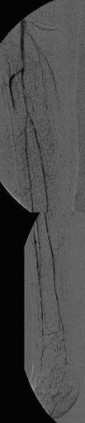

Vor perkutaner transluminaler Angioplastie (PTA) der Unterschenkelgefäße

(Bild 3 von 4)

Nach perkutaner transluminaler Angioplastie (PTA) der Unterschenkelgefäße

(Bild 4 von 4)